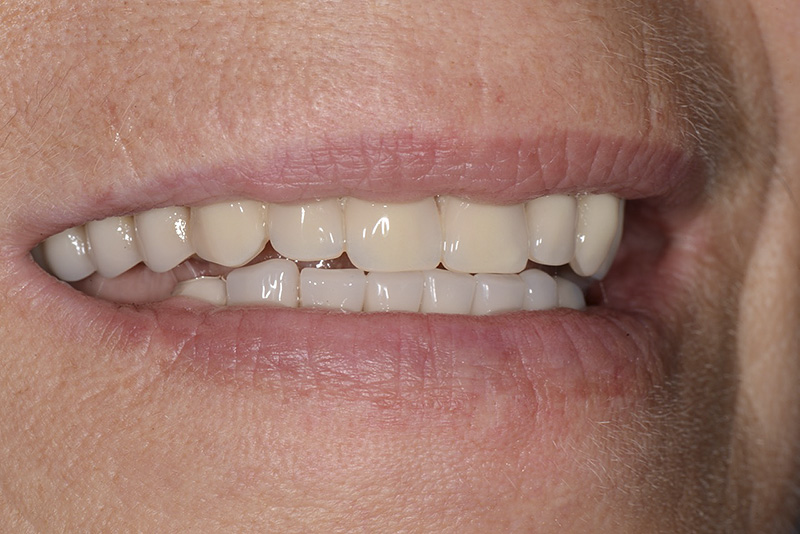

Vengono utilizzati 2 tipi di provvisori: il primo, cementato ai denti vicini, viene utilizzato dal momento dell’estrazione del dente fino ad impianto osteointegrato (circa 6 mesi); il secondo, avvitato direttamente all’impianto, ha una funzione di prova estetica ma soprattutto di guida per la maturazione dei tessuti gengivali peri-implantari portandoli verso la maturazione completa prima di posizionare la corona finale in disilicato di litio.